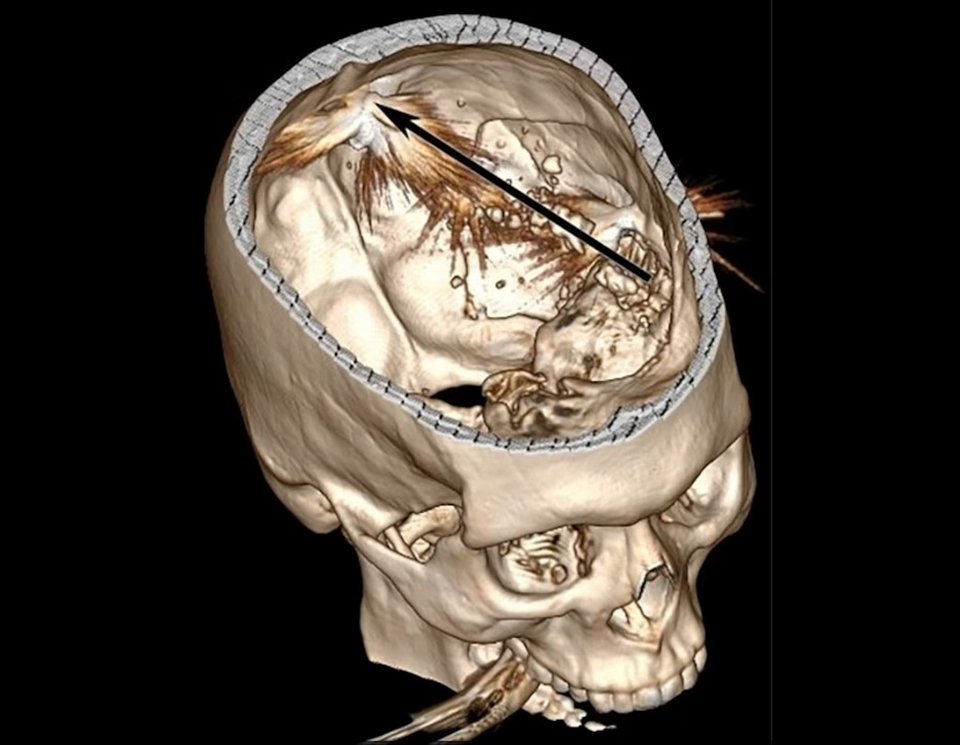

Άρθρο του αμερικανικού ιατρικού περιοδικού «American Journal of Case Reports» αναφέρεται στο «θαύμα» ενός αγρότη από την Κρήτη που δέχθηκε σφαίρα στο κεφάλι και επέζησε με μόλις 3% πιθανότητες επιβίωσης.

Ο 29χρονος αγρότης από την Κρήτη πυροβολήθηκε με πιστόλι από απόσταση περίπου 10 μέτρων, μεταδίδει η Daily Mail σε δημοσίευμά της. Η σφαίρα θρυμματίστηκε καθώς διέσχισε το αριστερό ημισφαίριο του εγκεφάλου του και κατέληξε κοντά στο πίσω μέρος του κρανίου του.

0 29χρονος μεταφέρθηκε εσπευσμένα στο νοσοκομείο σε «κωματώδη κατάσταση» μία ώρα μετά τον πυροβολισμό, με τους γιατρούς να πραγματοποιούν επείγουσα χειρουργική επέμβαση όπου αφαίρεσαν μέρος του κρανίου του για να ανακτήσουν τα θραύσματα της σφαίρας. Κάποια δεν μπόρεσαν να αφαιρεθούν, ανέφερε το περιοδικό.

3% πιθανότητες επιβίωσης από πυροβολισμό στο κεφάλι

Σύμφωνα με εκτιμήσεις, λιγότερο από το τρία τοις εκατό των ανθρώπων επιβιώνουν από τραύμα στο κεφάλι από πυροβολισμό. Από αυτούς, ακόμη λιγότεροι αναρρώνουν πλήρως από τα τραύματά τους και καταφέρνουν να ζουν όπως ζούσαν πριν τον σχεδόν θανάσιμο τραυματισμό.

Δυόμισι χρόνια μετά τον πυροβολισμό στο κεφάλι, ο άνδρας είναι ακόμη ζωντανός – αλλά δεν είναι πλέον σε θέση να μιλάει παρά μόνο με «μονοσύλλαβες “εκφράσεις”» και δυσκολεύεται να κατανοήσει σύνθετη γλώσσα.

Υποφέρει επίσης από ακούσιους σπασμούς στη δεξιά πλευρά του σώματός του και δυσκολίες στην κίνηση των μυών στην αριστερή πλευρά.

Παρ’ όλα αυτά, οι ερευνητές δήλωσαν ότι εξακολουθεί να έχει συναισθήματα και είναι σε θέση να σηματοδοτεί τις επιθυμίες του με ήχους και τους μύες του προσώπου του. Τα μέλη της οικογένειας είπαν επίσης στους γιατρούς ότι είναι βέβαιοι ότι θυμάται προηγούμενα γεγονότα, αν και δεν προσκομίστηκαν αποδείξεις γι’ αυτό.

Η σφαίρα διαπέρασε την αριστερή πλευρά του εγκεφάλου του – η οποία εμπλέκεται στην ομιλία και στην επεξεργασία της γλώσσας και στην καθοδήγηση των κινήσεων στη δεξιά πλευρά του σώματος.

Η δεξιά πλευρά, η οποία εμπλέκεται στα συναισθήματα και στην επίλυση προβλημάτων και στις κινήσεις της αριστερής πλευράς, δεν έπαθε τίποτα. Το περιστατικό αποκαλύφθηκε στην αμερικανική επιθεώρηση «American Journal of Case Reports» από γιατρούς του Γενικού Πανεπιστημιακού Νοσοκομείου Ηρακλείου.

Άγνωστο αν ήταν ατύχημα ή απόπειρα δολοφονίας

Δεν ήταν σαφές πού συνέβη ο τραυματισμός ή γιατί ο άνδρας είχε πυροβοληθεί- αν επρόκειτο για ατύχημα ή για σκόπιμη επίθεση.

Οι περισσότεροι άνθρωποι που πυροβολούνται στο κεφάλι πεθαίνουν σχεδόν αμέσως είτε από σοκ είτε επειδή διακόπτονται ζωτικές λειτουργίες. Μια περιοχή του εγκεφάλου στη βάση του ελέγχει ενέργειες όπως η αναπνοή και ο καρδιακός παλμός, με αυτές να σταματούν αν υποστεί βλάβη – και ο θάνατος να ακολουθεί αμέσως μετά.

Σε σπάνιες περιπτώσεις, ωστόσο, οι ασθενείς επιβιώνουν εάν η βλάβη στον εγκέφαλο δεν επηρεάζει κρίσιμες δομές και λαμβάνουν γρήγορα ιατρική φροντίδα. Αυτό συνέβη με τον ασθενή από την Κρήτη.

Αυτό σημαίνει ότι είναι δυνατόν να επιβιώσει κανείς από έναν τραυματισμό στην περιοχή, αν και τα άτομα θα είναι πιθανότατα ανάπηρα για το υπόλοιπο της ζωής τους. Οι γιατροί δήλωσαν ότι αποκαλύπτουν την περίπτωση για να δείξουν πώς ο εγκέφαλος μπορεί να ανακάμψει μετά από τραυματισμό στο αριστερό ημισφαίριο.

Τι διέγνωσαν οι γιατροί

Σε αυτή την περίπτωση, ο άνδρας αναφέρθηκε ότι υπέστη εκτεταμένη βλάβη στο αριστερό εγκεφαλικό, και στο αριστερό παρεγκεφαλιδικό ημισφαίριο – που συνδέεται με τον έλεγχο των κινήσεων. Οι γιατροί έκαναν αμέσως ράμματα στο τραύμα και πραγματοποίησαν χειρουργική επέμβαση για να μειώσουν την πίεση στον εγκέφαλο και να αφαιρέσουν τα θραύσματα της σφαίρας.

Αυτό έγινε μέσω μιας επείγουσας κρανιεκτομής – μιας χειρουργικής επέμβασης που περιλαμβάνει την αφαίρεση μέρους του κρανίου για την ανακούφιση της πίεσης στον εγκέφαλο. Νοσηλεύτηκε για δυόμισι μήνες, κατά τη διάρκεια των οποίων υποβλήθηκε επίσης σε κρανιοπλαστική – ή μερική ανακατασκευή του κρανίου – πριν μεταφερθεί σε κέντρο αποκατάστασης για 18 μήνες.

Δύο χρόνια μετά τον τραυματισμό, τον επανέφεραν στο νοσοκομείο για έλεγχο. Οι γιατροί διέγνωσαν ότι πάσχει από σοβαρή αφασία ή σοβαρές δυσκολίες επικοινωνίας που τον αφήνουν να δυσκολεύεται να κατανοήσει τη γλώσσα.

Διαπίστωσαν όμως ότι ήταν σε θέση να ακολουθήσει βασικές οδηγίες, όπως να καταλάβει σε ποιον από δύο ανθρώπους να δώσει ένα στυλό, αφού έλαβε οδηγίες. Διαπίστωσαν επίσης ότι ήταν σε θέση να παράγει ήχους ως απάντηση σε οδηγίες ή να εκφράζει συναισθήματα, όπως η επιθυμία να πάει σπίτι.